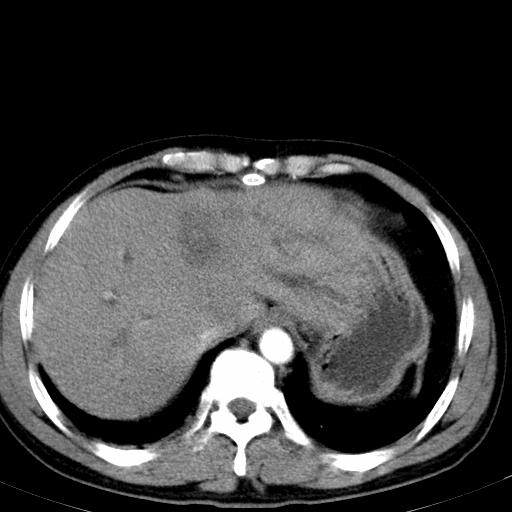

患者上腹部疼痛一月余,伴巩膜黄染;

实事求是的说,强化效果很一般,重点部位应重点观察,但有一点可以明确:肝门部胆管细胞癌。

考虑肝左叶胆管细胞癌侵犯肝门区并肝内胆管及肝总管扩张。

肝左叶肿块清度增强,所在的叶胆管扩张。考虑胆管细胞癌。